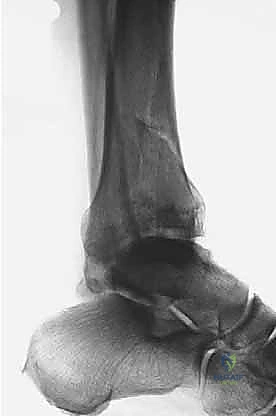

1. التصوير بالأشعة السينية التقليدية (X-Rays)

يتم أخذ صور من ثلاث زوايا (أمامية خلفية AP، جانبية Lateral، ومورتيس Mortise). تعطي هذه الصور فكرة عامة عن نمط الكسر، قصر الساق، ومدى انزياح العظام.